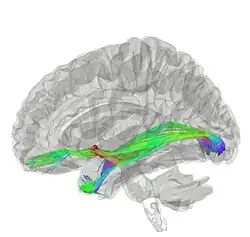

La commissure antérieure, appelée également la commissure blanche antérieure ou encore la précommissure (en latin : commissura anterior), est une commissure inter-hémisphérique qui croise transversalement la paroi antérieure du troisième ventricule[1]. C'est un faisceau nerveux de substance blanche (un paquet d'axones) qui relie les deux lobes temporaux des hémisphères cérébraux à travers la ligne médiane, et il se trouve en avant des colonnes du fornix (les piliers antérieurs trigone du cerveau). Chez la plupart des mammifères existants, la grande majorité des fibres reliant les deux hémisphères traversent le corps calleux, qui est plus de 10 fois plus grand que la commissure antérieure, et d'autres voies de communication passent par la commissure de l'hippocampe ou indirectement, via des connexions sous-corticales. Néanmoins, la commissure antérieure est une voie importante qui peut être distinguée clairement dans les cerveaux de tous les mammifères.

Les fibres de la commissure antérieure peuvent être tracées latéralement et postérieurement de chaque côté au-dessous du corps strié vers la substance du lobe temporal.

Elle sert à relier les deux lobes temporaux, mais il contient également des fibres décussantes des tractus olfactifs, et fait partie du tractus néospinothalamique pour la douleur. La commissure antérieure sert ainsi à relier les deux amygdales.

Le fonctionnement de la commissure antérieure demeure pas encore élucidé complètement. Les chercheurs l'ont impliqué dans plusieurs fonctions allant de la perception des couleurs à l'attention. Une de ces études a soutenu la perception des couleurs dans l'agénésie du corps calleux (Ceux nés sans corps calleux; Barr & Corballis, 2002)[6]. D'autres études se sont appuyées sur cela pour impliquer que la commissure antérieure peut être une voie compensatoire chez les personnes sans corps calleux, présentant des techniques d'imagerie diffusion pour mieux élucider la commissure antérieure et comment elle pourrait être impliquée dans diverses fonctions (Winter & Franz, 2014).